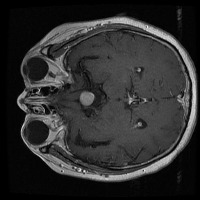

Early Detection of Brain Tumors: Use the "tesis" model to analyze MRI scans of patients proactively during routine check-ups, helping in the early identification of the presence of lesion selar or tumor hipofisario, leading to timely and potentially life-saving interventions.

Assisting in Treatment Planning: Oncologists and neurosurgeons can use the "tesis" model to study the location, size, and class of a patient's tumor. This helps in determining the best treatment options and surgical approaches, ultimately improving patient outcomes.

Medical Education and Training: Incorporate the "tesis" model in medical school curricula and professional trainings aimed at educating future doctors and radiologists about the identification and treatment of lesion selar and tumor hipofisario.

Research Tool for Cancer Studies: The "tesis" model can serve as a tool for researchers working on experimental treatments or clinical trials focused on lesion selar and tumor hipofisario. By identifying tumor classes efficiently and consistently, the model can help researchers compare treatment efficacy and study tumor progression over time.

Second Opinion Provider: Medical professionals can use the "tesis" model to double-check their own findings when analyzing brain MRI scans. This can reduce the likelihood of diagnostic errors and help confirm the presence of lesion selar or tumor hipofisario, resulting in more accurate decision-making.